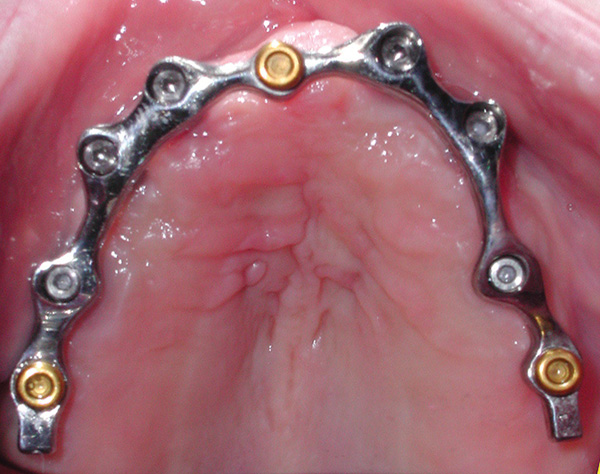

A-P ratio refers to the distance between the most anterior implant(s) (the A) and a line drawn between the most posterior implants (the P). The distance between the two lines is measured, and that determines how far posteriorly the prosthesis can be cantilevered. Accepted distance allows for 1 to 1.5 times the A-P ratio to be cantilevered distal to the most posterior implant.3,4 Patients with ovoid arch forms typically allow better A-P ratio due to the available positions for the fixtures. A square arch form, on the other hand, tends to place the anterior and posterior implants closer together, creating a shorter A-P ratio and necessitating shorter cantilevers. This principle is applied in both the maxillary (Figure 11) and mandibular arches and, when followed, limits unwanted loading of the implants retaining the bar. A-P ratio is also relevant in the mandible when deciding how far distally the overdenture bar or fixed framework can be extended from the most distal implants. When the cantilever exceeds the recommended cantilever length based on A-P ratio, tensile loading occurs on the most anterior implants when occlusally loaded, with fulcruming occurring on the posterior implants. This may lead to loosening or fracturing of the prosthetic screw retaining the bar to the anterior implants and, depending on the bone quality, progressive bone loss of those anterior implants. When an anterior cantilever is present, which occurs typically in the maxilla with a square arch form due to resorption of the premaxilla, fulcruming would be seen on the anterior fixtures, with stresses placed on the posterior implants when occluding into food (eg, biting a sandwich or a whole apple) or habits that involve holding something in the anterior (eg, biting on a pen or pipe).

Fig 11. An ovoid arch form with the anterior line (A) and posterior line (P) providing a measurement between the two lines, which indicates how far posterior the prosthesis can be cantilevered.

Figure 11